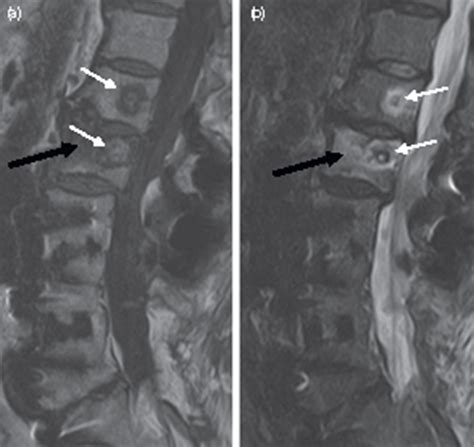

• Pre-Procedure Preparation: Before the procedure, patients undergo a thorough evaluation to determine if they are suitable candidates. This includes medical history, physical examination, and imaging tests such as MRI or CT scans.

• Have been diagnosed with vertebral endplate abnormalities, which are often associated with chronic low back pain.